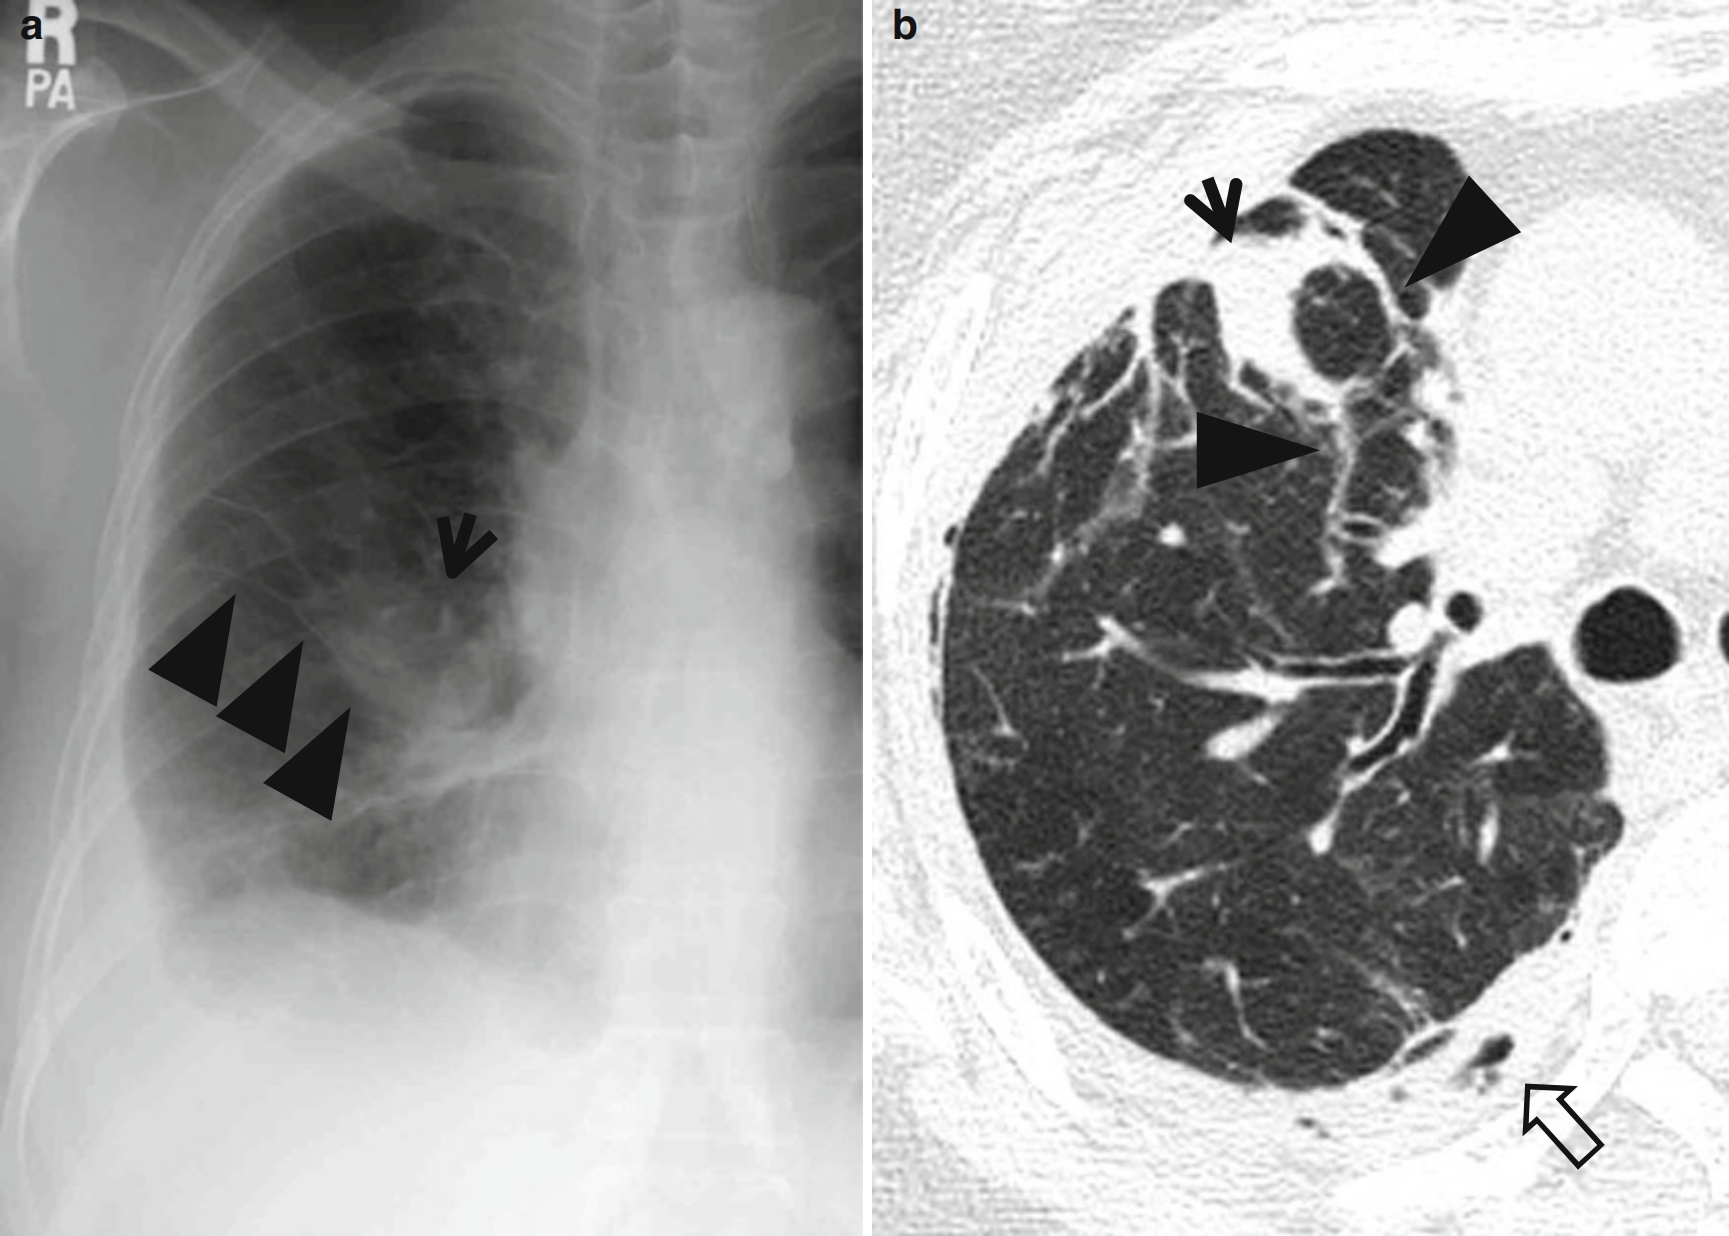

图1 圆形肺不张。

男,66岁,主诉气促和咳嗽。

(a)胸片显示:右侧胸腔积液和右中肺野水平裂(楔形箭头所示)上方肿块(箭头所示)。

(b,c)薄层CT(层厚=1.5mm)显示:分别在右上叶支气管分叉水平(b)和右肺中间段支气管水平(e),可见与前胸膜粘连的右肺上叶圆形肺不张(箭头所示);并可见血管性的条索状软组织密度影(楔形箭头所示),从圆形肺不张的后缘延伸至肺门。另可见右后部胸腔积液和胸膜增厚(空心箭头所示)。

(d)与c图相同位置软组织窗显示右肺上叶圆形肺不张(箭头所示),同时可见右侧胸腔积液和胸膜增厚。